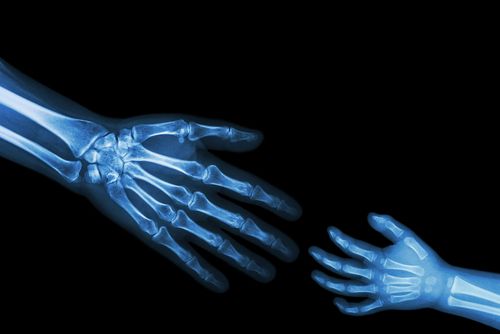

Case History: 27-year-old patient presented with history of trauma.